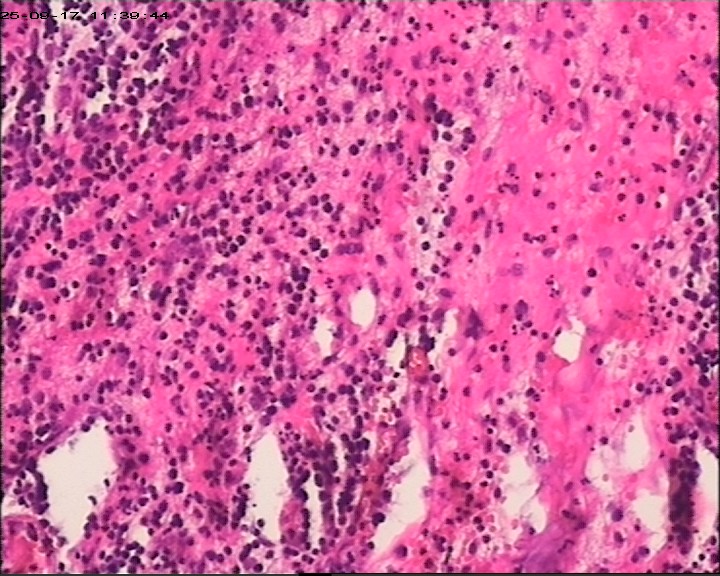

臀部组织,请帮忙看看,谢谢

性别

男

年龄

20岁

临床诊断

一般病史

藏毛窦或囊肿切开术

标本名称

臀部

大体所见

灰白灰黄碎组织一堆,大小为6.5*4*1cm。

描述诊断炎性病变